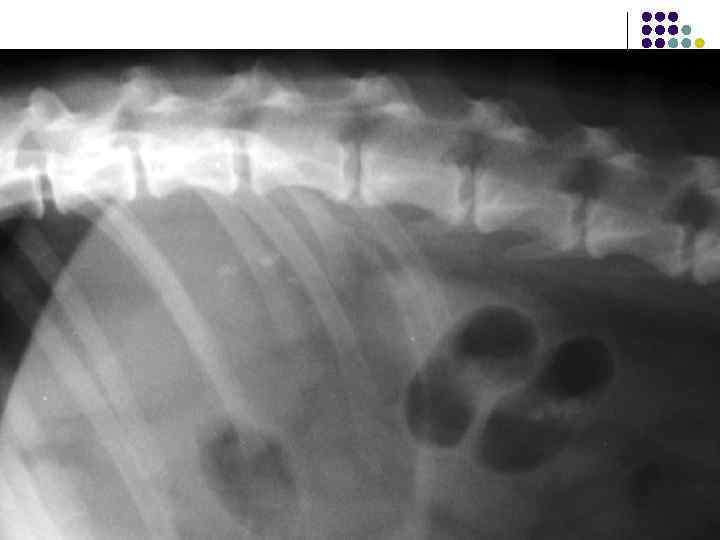

Камни мочевого пузыря